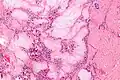

Gross pathology of a large tophus Micrograph of a gouty tophus

Micrograph of a gouty tophus A tophus inside a knee joint being removed by arthroscopic surgery